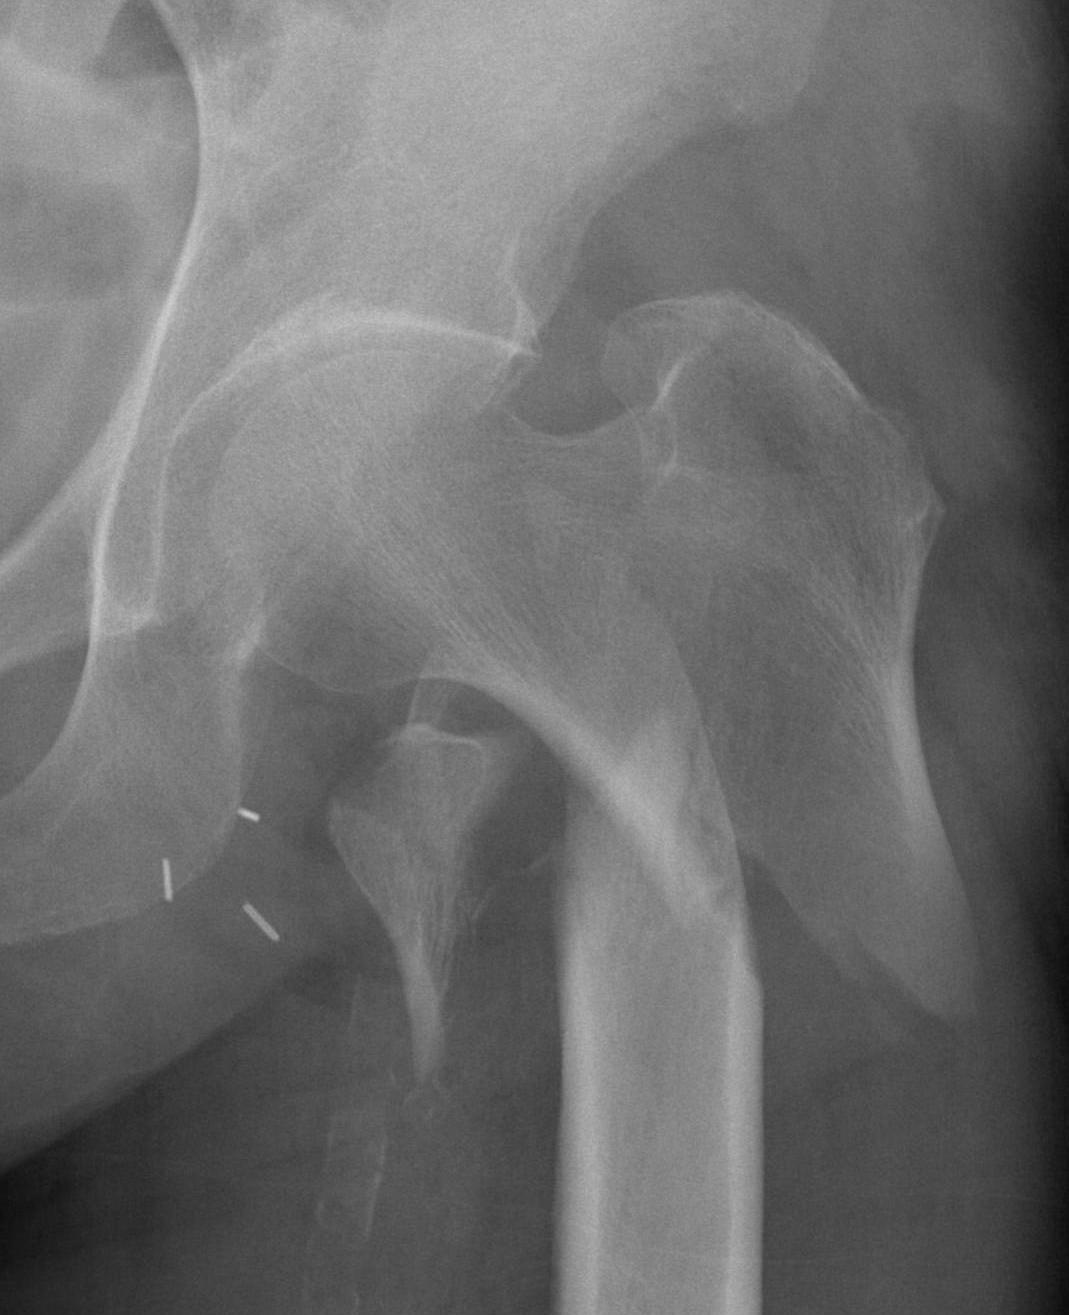

Malreduction

Screw cut out

Malreduction

Screw Cut

Causes

- malreduction

- poor screw position / high tip apex distance

- poor bone quality

- Retrospective review of 198 intertrochs treated DHS

- none < 25mm cutout. > 25mm strong predictor of cut-out

Malunion

Excessive lateral sliding / shaft medialisation

Cause

- collapse with insufficent lateral buttress

- reverse obliquity fracture